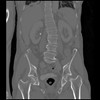

6 CUERPO,CE,Coronal,3.000,CUERPO,Coronal,